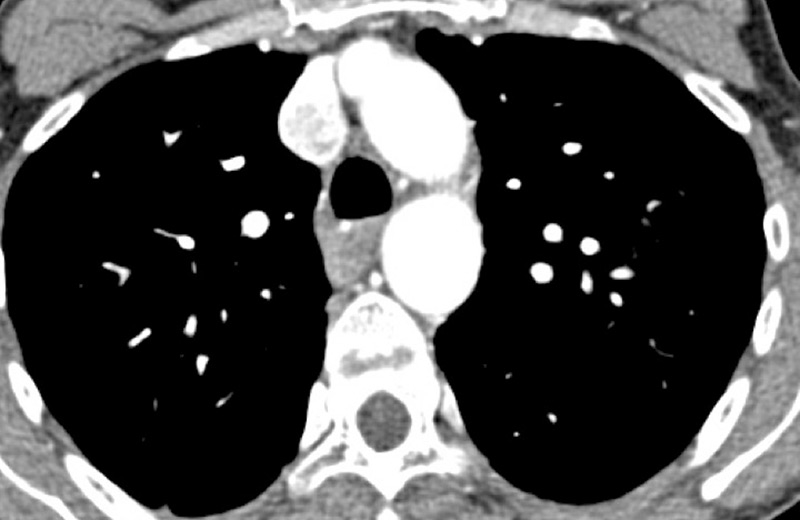

Figure 2

Chronic thromboembolic pulmonary hypertension (CTEPH). Vascular (A) and parenchymal (B) signs of CTEPH with proximal marginal occlusion (arrows) and mosaic pattern (stars). Functional information simply added with triangular perfusion defects (stars) on the iodine maps (C).